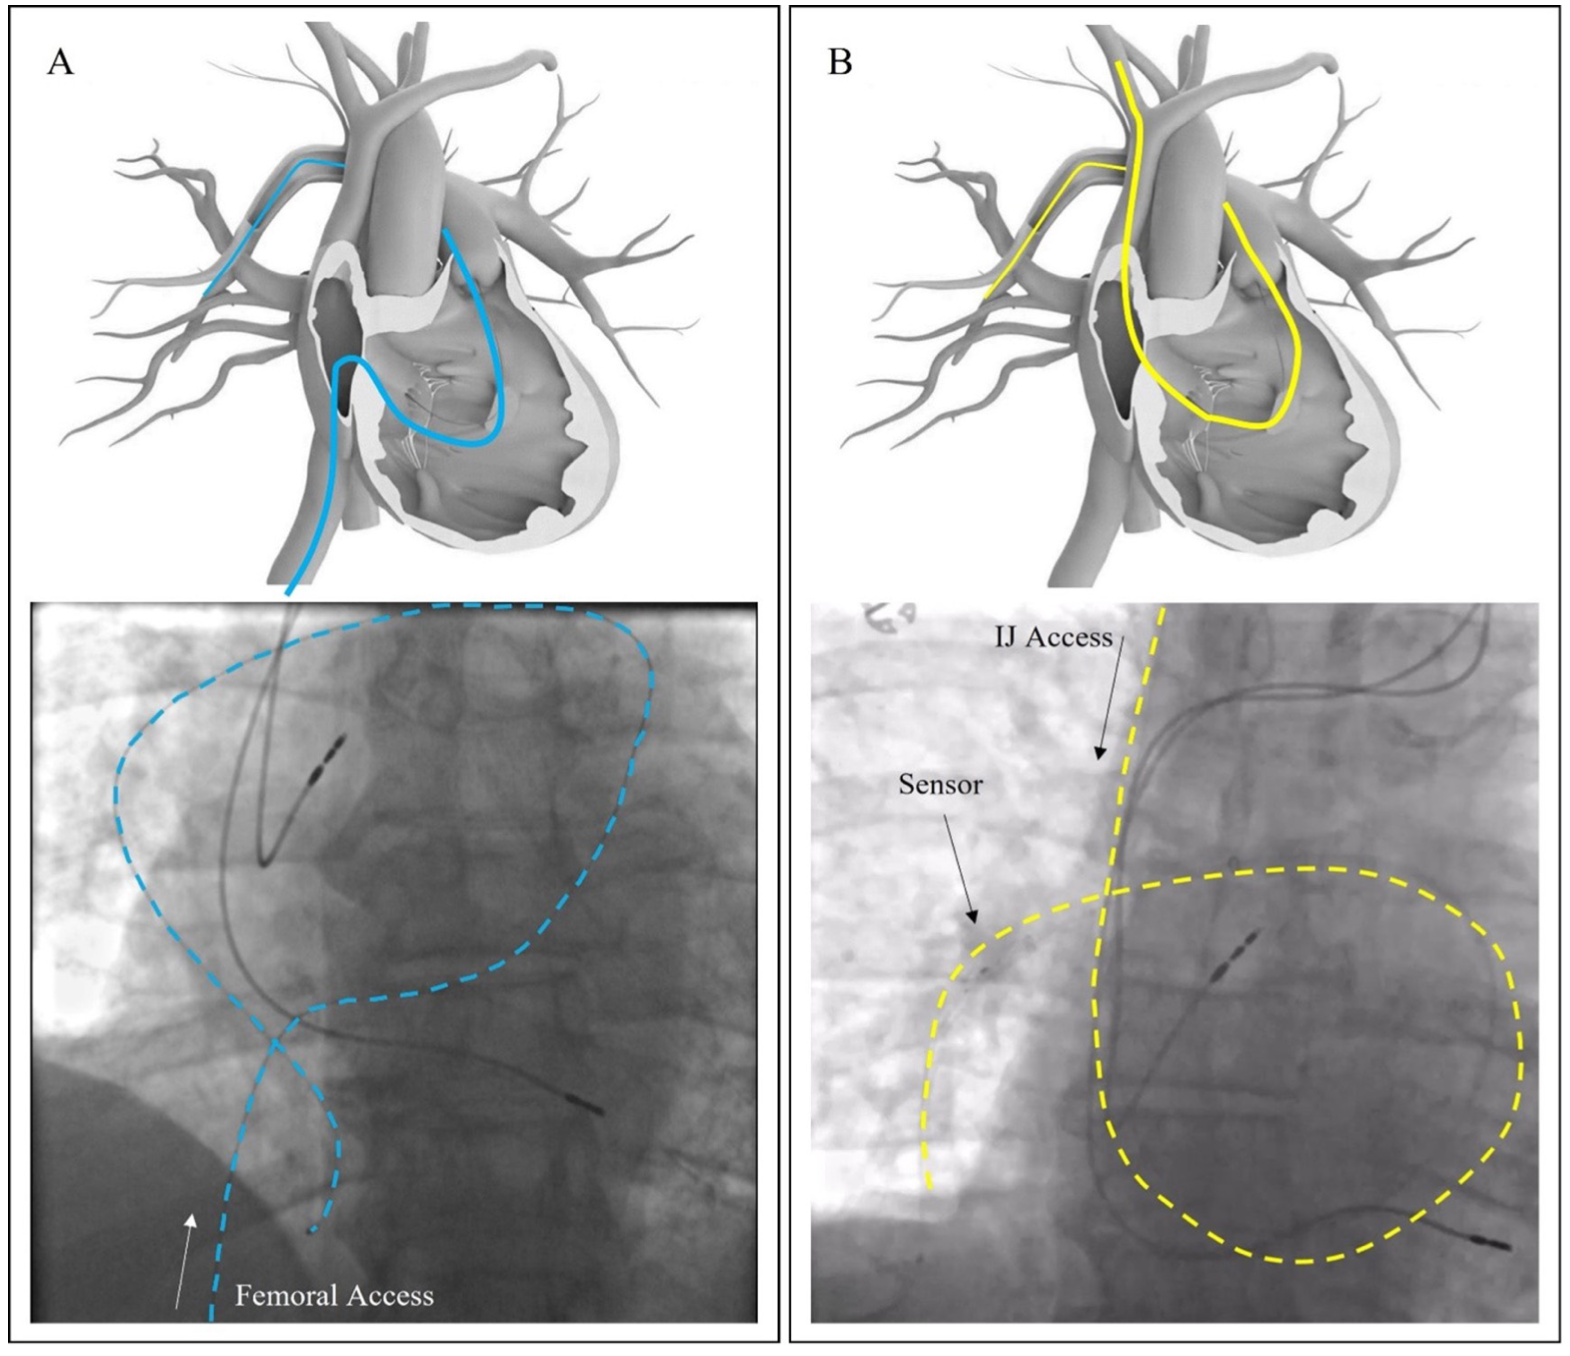

Remote monitoring of pulmonary artery (PA) pressures has been shown to reduce heart failure (HF) hospitalizations in patients with New York Heart Association (NYHA) class III HF symptoms, regardless of ejection fraction, more effectively than standard HF management.1-4 The Cordella PA pressure sensor system (Endotronix, Inc) has been shown to enable safe and accurate monitoring of HF patients in the first-in-human SIRONA trial (NCT03375710) and CE-Mark SIRONA 2 trial (NCT04012944) and is currently undergoing further investigation in the PROACTIVE-HF (NCT04089059) investigational device exemption trial.5-7 The sensor is percutaneously placed exclusively in the right pulmonary artery (RPA), where the interlobar artery typically turns downward and posterior and has a vessel diameter of 12-26 mm (Figure 1).8 After implantation, the patient can take daily readings from home via a handheld patient reader placed on the anterior right chest, from either a seated or supine position, and the sensor data are read wirelessly and transmitted automatically to the care team. The reading provides an 18-second measurement of PA pressures, allowing for remote adjustment and optimization of medical therapy to align with prespecified PA pressure goals. The goal of the present review is to provide an overview of the implantation process and present a series of cases highlighting various clinical situations and/or challenges that may arise during sensor implantation.

Prior to the presented case, the majority of Cordella implants were completed using femoral vein access with low complication rates comparable to a commercially available PA pressure sensor. Despite many years of using this approach, groin complications remain a significant challenge even when advanced techniques such as ultrasound guidance and micropuncture are employed. Moreover, patient anatomy and/or medical history may pose additional challenges to this technique. As demonstrated in the case presented here, the presence of iliac vein compression prevented femoral access in this case. The IJ access was easily achieved and supported the implantation of the Cordella sensor without challenge. In fact, the anatomy of the RIJ approach formed a “6” as opposed to the more tortuous “S” shape of the femoral approach when traversing the cardiac anatomy (Figure 5). Additional advantages of IJ access include ability to forgo bedrest following the procedure, allowing for faster patient training and discharge, and increasing the throughput in the cardiac catheterization lab, which has potential economic implications.10,11 Most importantly, by having more techniques to implant the Cordella sensor, more patients can benefit from the next generation remote patient management offered by this system. Of note, the currently used protocol fully supports implanters to choose between the femoral and IJ access sites without issuing protocol deviations or requiring medical necessity for either technique.